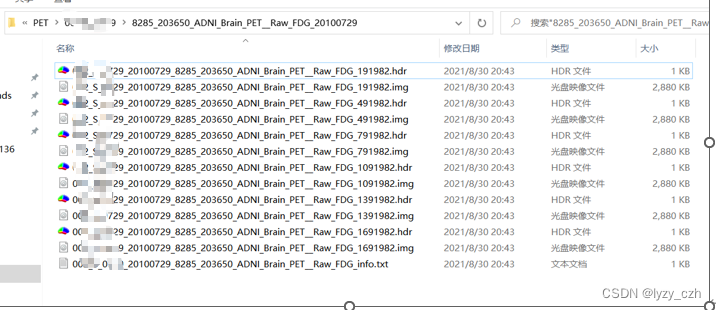

转换完成后输出如下:

这里生成了多个hdr/img的图像,只需要选择其中最好的一个即可(我看起来都是一样的)